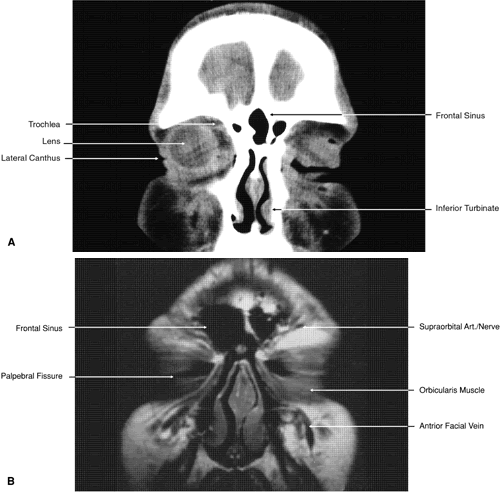

The globe is shown in Figure 12. The orbit and periorbital structures are shown in Figures 13 through 16, and the optic canal is shown in Figures 17 through 26. The cavernous sinus and optic chiasm are shown in Figures 27 and 28, and the posterior visual pathway and cranial nerves are shown in Figures 29 through 33.

Fig. 17. Coronal images through anterior orbit. A. Computed tomography scan. B. T1-weighted magnetic resonance imaging.

Fig. 18. Coronal images through midglobe. A. Computed tomography scan. B. T1-weighted magnetic resonance imaging.